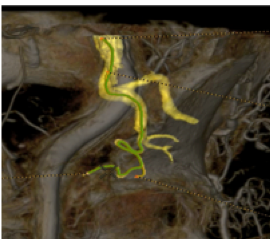

Planifier